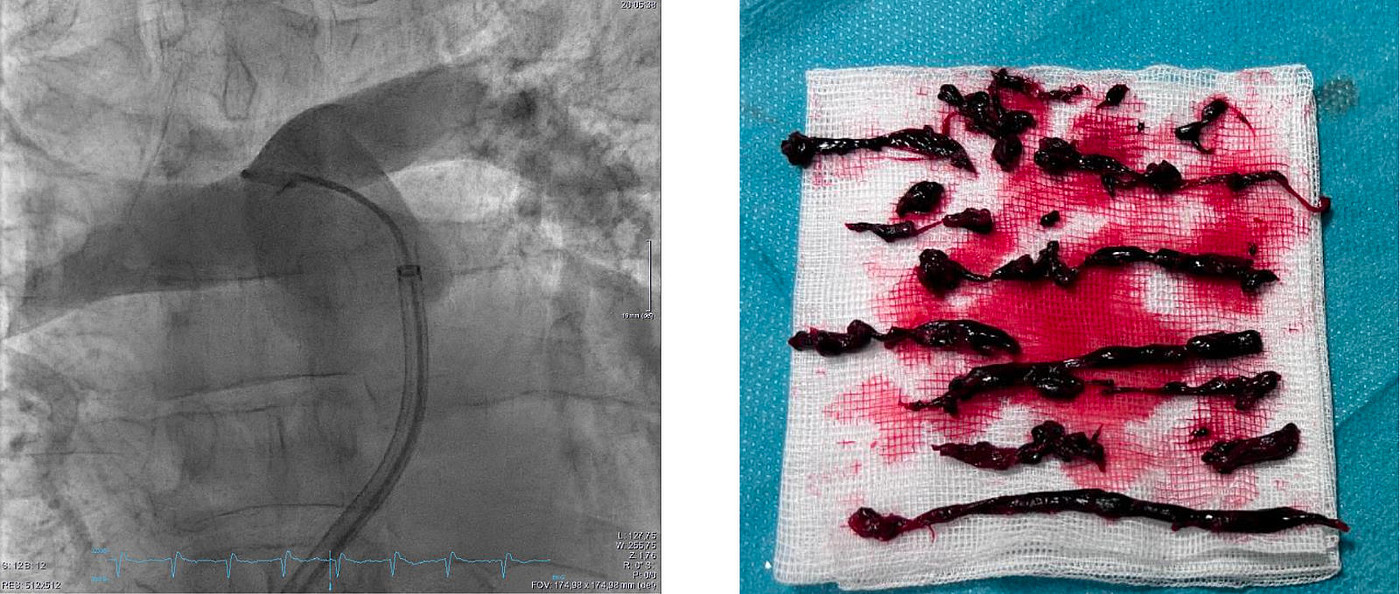

In der Studie werden kathetergestützte Therapieverfahren bei Patient:innen mit intermediär-hochrisiko Lungenembolie untersucht. Diese minimalinvasiven Ansätze sollen die Versorgung verbessern und Komplikationen reduzieren – insbesondere bei Menschen mit erhöhtem Risiko. Mit dem erfolgreichen Einschluss des ersten Patienten in Deutschland stärkt die UMM ihre Rolle als Studienstandort und erweitert gleichzeitig das Behandlungsspektrum im Bereich der interventionellen Lungenembolietherapie.